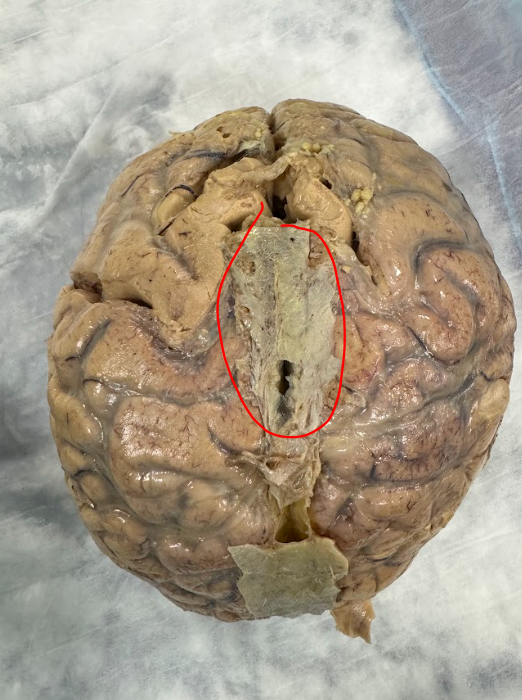

3rd ventrical